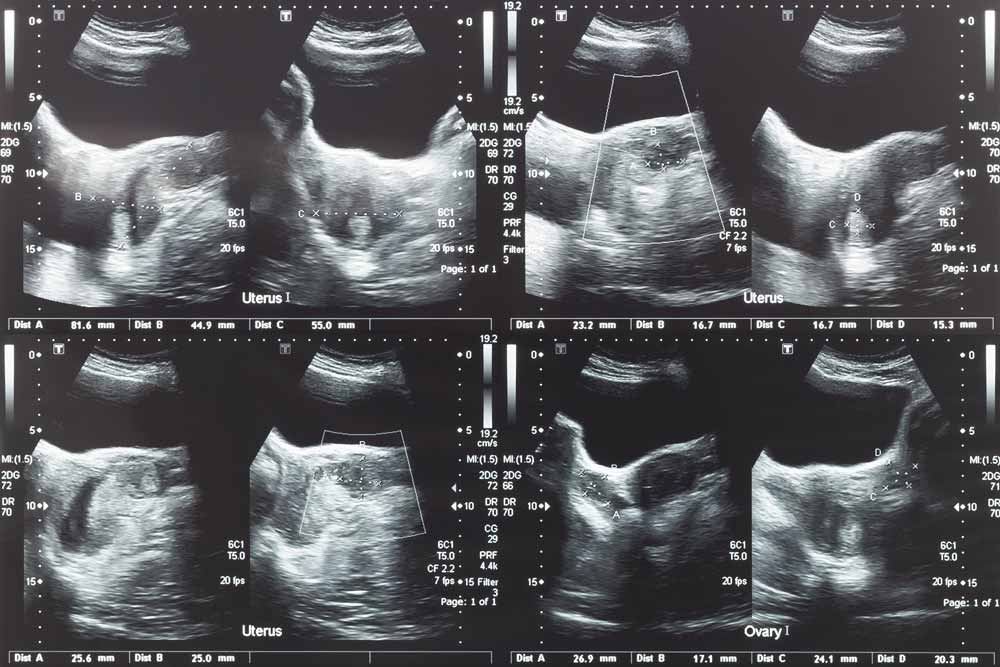

- Pelvic Female - ovaries, uterus, bladder